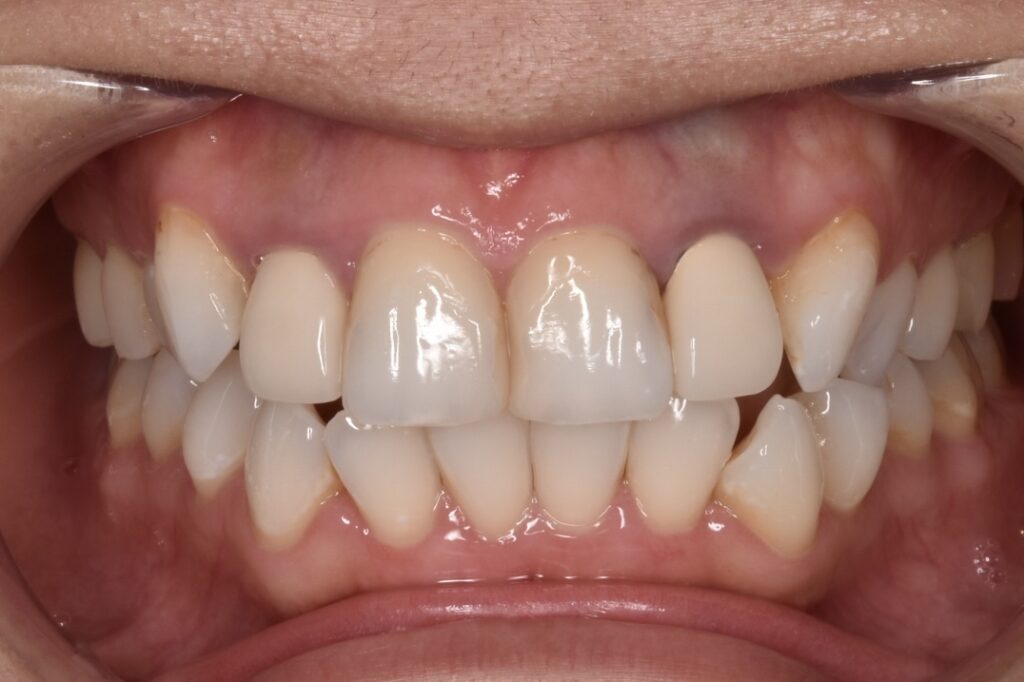

モニター様①

こちらのお客様は全ての銀歯と古い被せ物をやりかえしてくださったモニター様です。上の前歯と下の歯の犬歯がよくわかります。見える部分の銀歯も無くなりました。*ダイヤモンド匠プラン